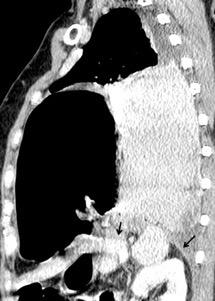

Diafragma “colgante” (“dangling sign”)

(“Dangling sign”)

TC. Mejor con multicorte. (reconstrucciones).

Asociación: Aire en pared.

Fracturas costal .Rotura esplénica. Neumoperitoneo.

Diafragma discontinúo Herniación de la grasa omental

Desser TS et al.The dangling diaphragm sign: sensitivity and comparison with existing CT signs of blunt traumatic diaphragmatic rupture. Emerg Radiol 2010